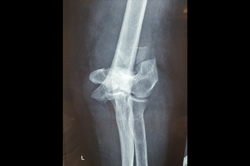

Proximal Tibia